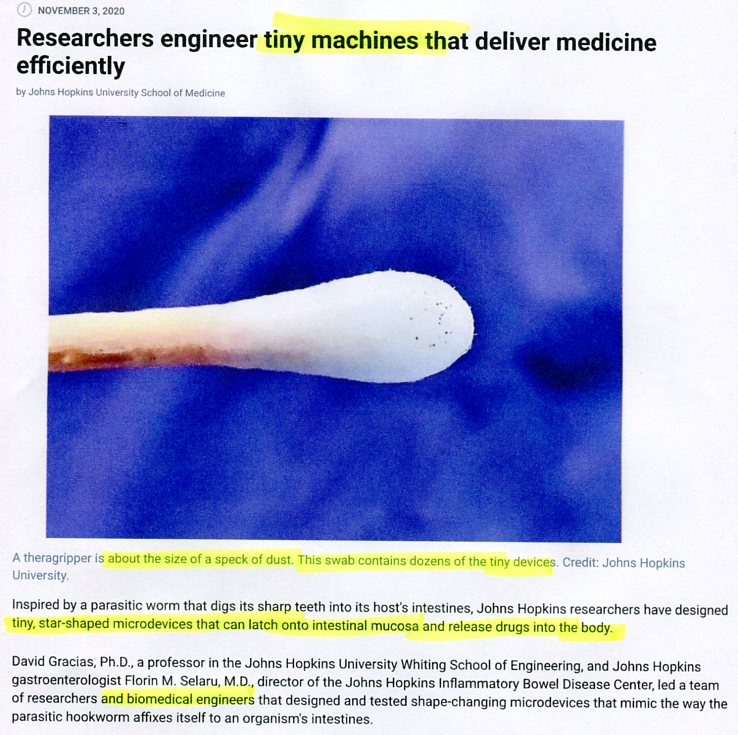

COVID INJECTS GMO TRACKING DEVICE

Genetically Engineered COVID Vaccine Being Made

COVID-19 AGENDA CERTIFICATE OF VAX ID BY AI

Scientific American, Dec 3, 2021

watch Covid swab test contains micro-machines listen

(nanotech devices turn humans into cell-phones)